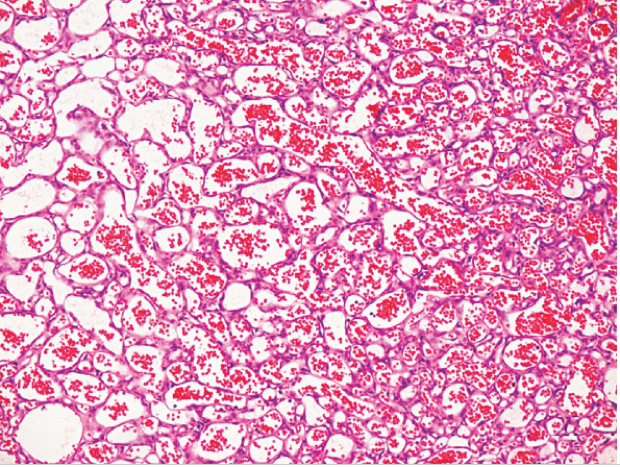

3.血管瘤(hemangioma)

多为先天性,常见于儿童的头面部皮肤。内脏血管瘤以肝脏最多见。病理学将血管瘤分为毛细血管瘤(由增生的毛细血管构成)、海绵状血管瘤(由扩张的血窦构成)及混合型血管瘤(即两种改变并存)三种。上无包膜,呈浸润性生长,在皮肤或粘膜可呈突起的鲜红斑块,或呈暗红、紫红色斑,内脏血管瘤多呈结节状。血管瘤一般随身体发育而长大,成年后即停止发展,较小者可自然消退。

毛细血管瘤

| 海绵状血管瘤